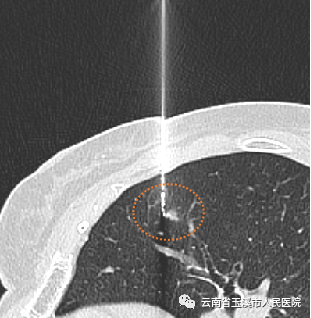

CT引导下肺小结节术前辅助定位就成为了有效的手段。在临床使用中安全可靠、成功率高、并发症少,可为临床医生在术中快速准确探寻结节位置、最大限度精准切除肿瘤,并给病理科医生提供精准的切片范围,不仅缩短了患者手术时间、降低手术风险,而且可较大限度保护患者肺组织肺功能。目前,玉溪市人民医院已成功的进行了多例CT引导下肺结节穿刺术前定位,穿刺过程顺利,手术成功。

CT呈像浸润性腺癌引导定位

据了解,玉溪市人民医院医学影像部现已常规开展CT引导下经皮穿刺肺小结节辅助定位及活检手术,发现早期肺癌,避免患者因发现较晚发生转移而遭受放化疗的痛苦,提高生活质量,提高患者生存率。同时,这项技术的推广应用也可更好的为玉溪及周边地区的体检客户及患者做好肺结节的筛查及诊断工作。